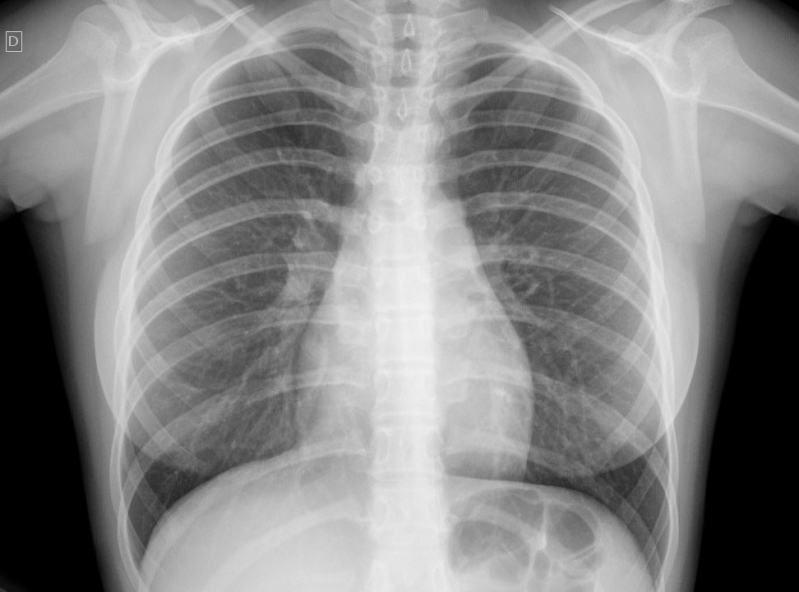

Impressora para Raio-x

RS IMPRESSORASUma impressora para raio-x deve ser específica para que haja o perfeito resultado, principalmente, se houver algum incoveniente que necessita de tratamento. Esse tipo de equipamento é...

Uma impressora para raio-x deve ser específica para que haja o perfeito resultado, principalmente, se houver algum incoveniente que necessita de tratamento. Esse tipo de equipamento é imprescindível em hospitais e clínicas.

Para uma peça de excelência, é de extrema autoridade contar com a ajuda de profissionais especializados e aptos a expandir um serviço de particularidade.

Deseja mais informações sobre impressora para raio-x?

Desenvolvendo um trabalho que oferece comodidade e certificando soluções inovadoras em outsourcing de impressão, a RS Impressoras é consolidada em seu segmento por conta da excelência apresentada em seus serviços.

Priorizando sempre as necessidades dos seus clientes, a empresa conta com uma equipe de profissionais elevadamente qualificados e aptos a expandir um serviço completo e de extrema particularidade.

Com experiencia a começar de 2007, a RS Impressoras garante a satisfação dos seus solicitantes, procurando sempre melhorias em cada um dos seus processos. Saiba mais entrando agora mesmo em contato!

Uma impressora para raio-x deve ser específica para que haja o perfeito resultado, principalmente, se houver algum obstáculo que necessita de tratamento. Esse tipo de equipamento é imprescindível em hospitais e clínicas.

Para uma peça de excelência, é de extrema seriedade contar com a ajuda de profissionais especializados e aptos a ampliar um serviço de particularidade.

Deseja mais informações sobre impressora para raio-x?

Desenvolvendo um trabalho que oferece comodidade e certificando soluções inovadoras em outsourcing de impressão, a RS Impressoras é consolidada em seu segmento por conta da excelência apresentada em seus serviços.

Priorizando sempre as necessidades dos seus clientes, a empresa conta com uma equipe de profissionais elevadamente qualificados e aptos a ampliar um serviço completo e de extrema particularidade.

Com experiencia doravante 2007, a RS Impressoras garante a satisfação dos seus solicitantes, procurando sempre melhorias em cada um dos seus processos. Saiba mais entrando agora mesmo em contato!